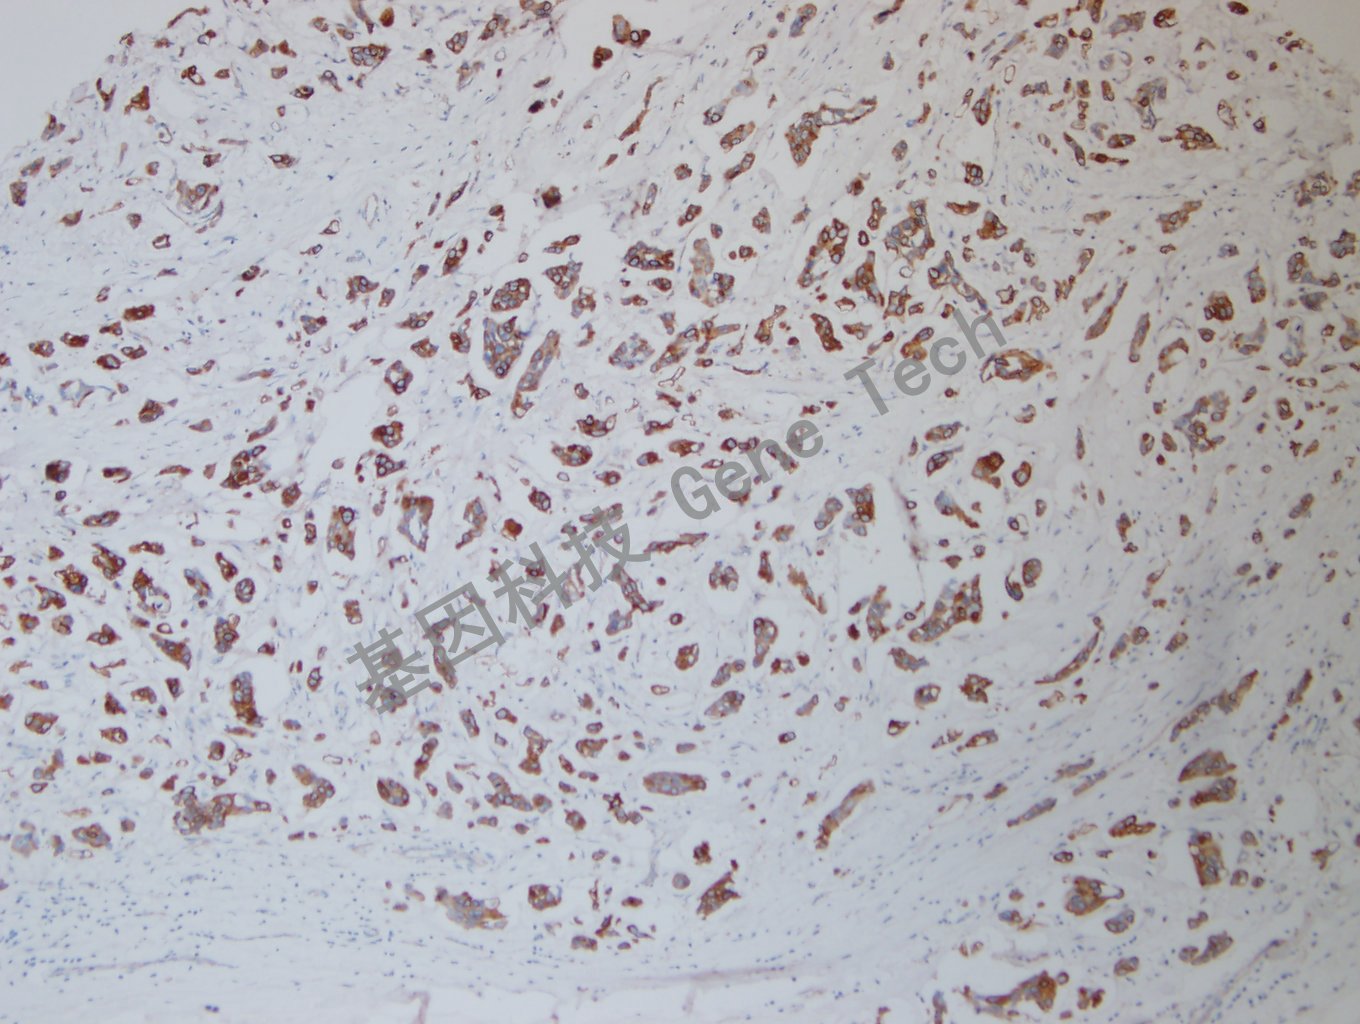

乳腺癌石蜡切片,用CK7(GT2446)染色,细胞浆阳性,DAB 显色。

乳腺癌石蜡切片,用CK7(GT2446)染色,细胞浆阳性,DAB 显色。(10×)